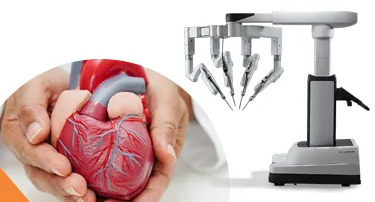

Robotic Heart Surgery in India: Benefits of da Vinci Xi for Complex Cardiac Conditions

Think of your expensive luxury watch; in case there is any defect, if you try to fix the delicate gears present inside the watch with large tools. What will happen? Chances are, even a small movement mistake could cause significant damage.